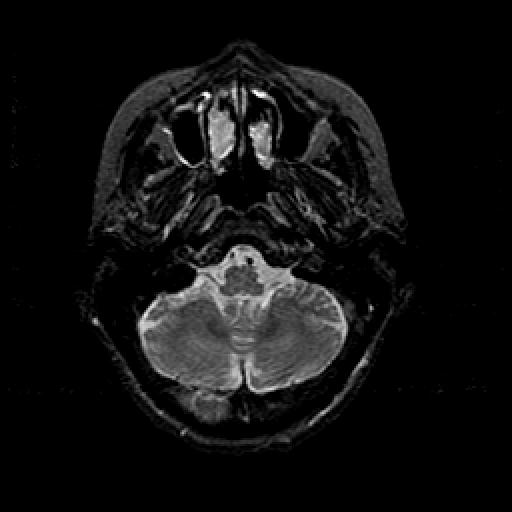

T2-weighted structural MR: Slice 11

Slice 11